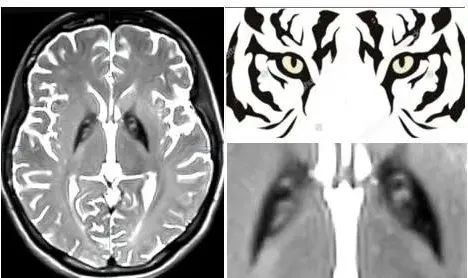

在完善头颅磁共振后,中山一院神经外科团队发现苗苗的双侧基底节区的苍白球内侧部(GPi)存在可疑“虎眼征”。

“我们考虑患者可能是遗传代谢性疾病,建议完善基因检查并采取了对症治疗措施。”神经外科副主任刘金龙教授说。基因结果提示患者的PANK2基因纯合突变,结合临床表现及基因检测结果,苗苗最终被确诊为原发性遗传性肌张力障碍,类型为泛酸激酶相关神经变性病(Pantothenate Kinase Associated Neurodegeneration, PKAN)。